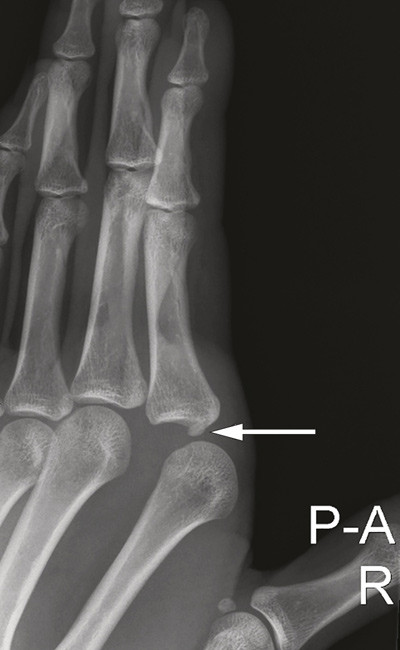

Den volare platen, en bindevevsplate som forsterker leddkapselen, bidrar til volar stabilitet ved metakarpofalangealleddet. Hos de fleste er det i enkelte av disse leddene «innebygd» sesambein i volarplaten. I en studie basert på røntgenbilder av 442 personer fra middelhavsland hadde 99,5 % sesambein ved første metakarpofalangealledd, nest vanligst var det ved annet metakarpofalangealledd (42,3 %), dernest ved femte (41,1 %) (2). Røntgenbildene av pasientens hånd viste et sesambein i leddspalten (pil), et patognomonisk tegn på at volarplaten, som sesambeinet er festet i, er rumpert og ligger låst mellom leddflatene. I slike tilfeller lukserer i tillegg caput metacarpale palmart og blir låst mellom sener, muskler og ligamenter. Dette er en kompleks luksasjon, som forekommer forholdsvis sjelden.